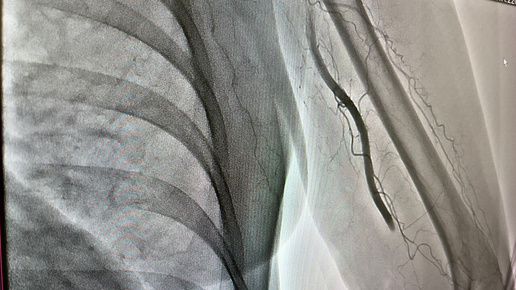

В Новокузнецке врачи извлекли 7-сантиметровый тромб, спасая женщину от ампутации руки

Министр здравоохранения Кузбасса Андрей Тарасов сообщил о случае, который произошел в Новокузнецке. В городской клинической больнице №1 имени Г.П. Курбатова врачи извлекли из плечевой артерии левой руки пациентки тромб длиной около семи сантиметров. Все началось с того, что женщина неожиданно почувствовала сильную боль в руке, после чего потеряла сознание. На вызов оперативно прибыла бригада скорой помощи, которая доставила пострадавшую в стационар. Обследование показало наличие острого нарушения кровотока, вызванного тромбозом...